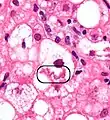

NASH (inflammation) and fibrosis stage 1

NASH (inflammation) and fibrosis stage 2

Lobular inflammation

NAFLD comprises two histological categories: NAFL, and the more aggressive form NASH. The presence of at least 5% fatty liver is common to both NAFL and NASH, but the features of substantial lobular inflammation and hepatocyte injuries such as ballooning or Mallory hyaline only occur in NASH. The majority of NAFL cases show minimal or no inflammation.[3][5][7] Pericentral and perisinusoidal fibrosis occur more often in adult-onset NASH, whereas portal fibrosis is more common in children with the disorder. NASH represents a more advanced stage of NAFL and is associated with poor outcomes such as cardiovascular events, cirrhosis, or hepatocellular carcinoma. ICD-11 does not use the term NAFL as it was deemed confusing with the family of disorders NAFLD. The preferred descriptions are instead: MAFLD without NASH or simple steatosis and "NASH". Also, the modifier with or without fibrosis or cirrhosis completes the diagnostic description.[3][7]

The primary characteristic of MASLD is the accumulation of lipids in the liver, largely in the form of triglycerides.[19] However, the mechanisms by which triglycerides accumulate and the reasons that accumulation can lead to liver dysfunction are complex and incompletely understood.[19][47][48] MASLD can include steatosis along with varied signs of liver injury: either lobular or portal inflammation (a form of liver injury) or ballooning degeneration. Similarly, NASH can include histological features such as portal inflammation, polymorphonuclear cell infiltrates, Mallory bodies, apoptotic bodies, clear vacuolated nuclei, microvesicular steatosis, megamitochondria, and perisinusoidal fibrosis.[16] Hepatocyte death via apoptosis or necroptosis is increased in MASH compared with simple steatosis, and inflammation is a hallmark of MASH.[32]